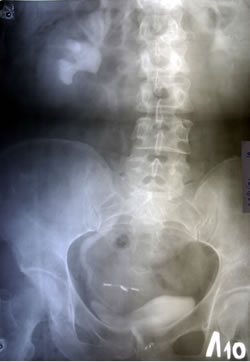

ОБЗОРНАЯ

УРОГРАФИЯ: |

|